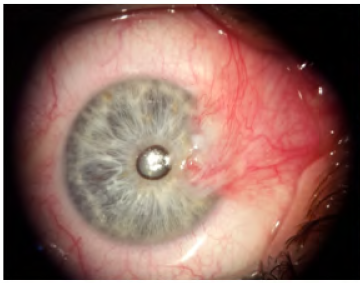

Case Series

A Case Series on Patients Having Preoperative Non-with-the-Rule Corneal Astigmatism and Showing Failure of Visual Improvement After Pterygium Excision

Fathy Fawzy Morkos, Maged Maher Roshdy, Mona Fathy, Tamer Abdelfattah Badran and Rania Serag Elkitkat. 14(6): 06-10.